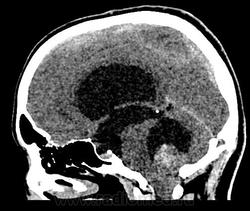

Девушка 30 лет. Поступила с диагнозом Эпилепсия. Неоднократные синкопы, начавшиеся после родов. Роды в начале марта, все благополучно. После родов, как-то так плохо все,шатает, голова болит. Через месяц обратилась в республиканскую больницу, выполнена кт- смешання гидроцефалия. Пролечили и выписали с диагнозом Дистония. Как-то так.

-признаки интравентрикулярной окклюзи выходных отверстий 4 желудочка, с резким расширением всех отдела желудочковой системы.

-резкое сужение охватвающей и большой цистерн

-выраженное расширение хиазмальной и предпонтийной цистерн

-истонены кости основания черепа,усилен рельеф внутренних костных пластин,углублено и расширено турецкое седло,опускание СЧЯ

-ствол и продолговатый мозг в дорсальном отделе уплощены,смещены вентрально

-в полости 4 желудочка объемное образование с учсатками кровоизлияния, с распространением каудально, признаки вклинения миндалин в БЗО,большая цистерна и САП кранио-вертебрального перехода не прослеживаются.